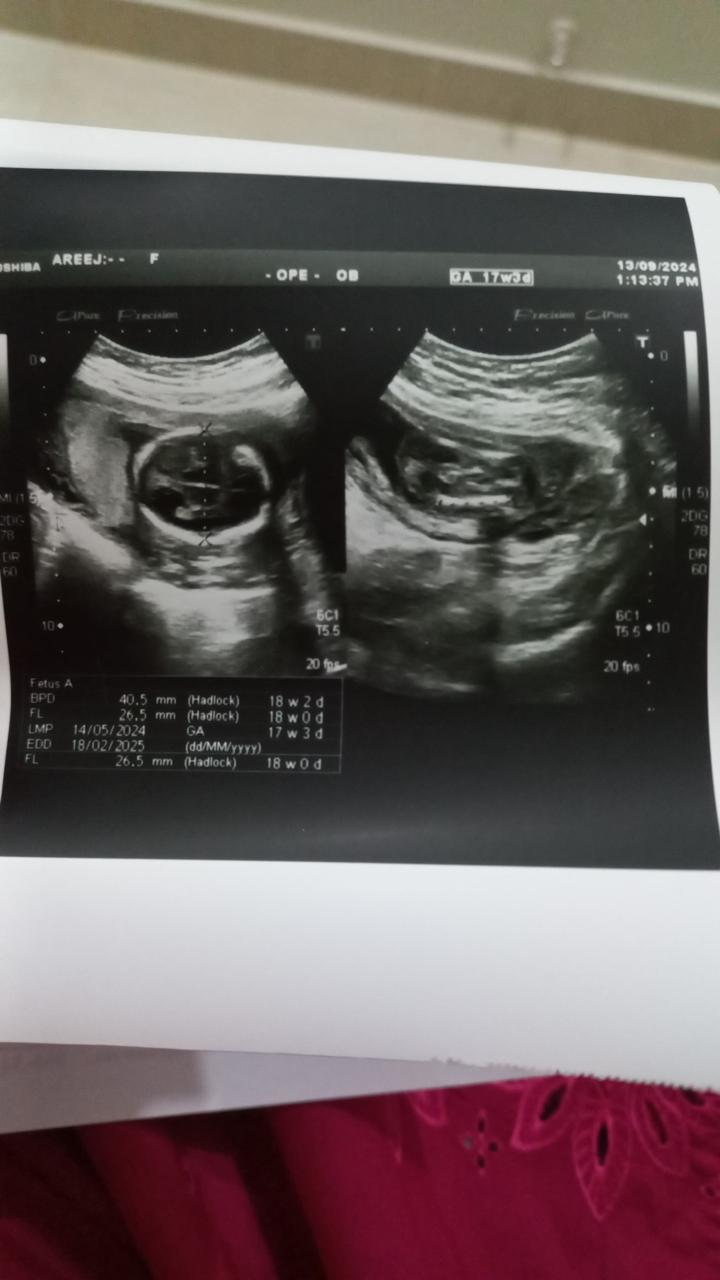

Doctor hope you are doing well. My wife is pregnant of 20 weeks 4 days now and her anomaly scan was done at around 18 weeks. According to reports the baby had lateral ventricle size 6mm other ventricles like left and right was normal. The doctor said come again after 21 week we will do your anomaly scan again. We are so worried and tense even not sleep well every day. I’ll attach the report. Can you please tell me is everything okay and could you please explain little bit. Thanks in advance,

Attach Photo here: